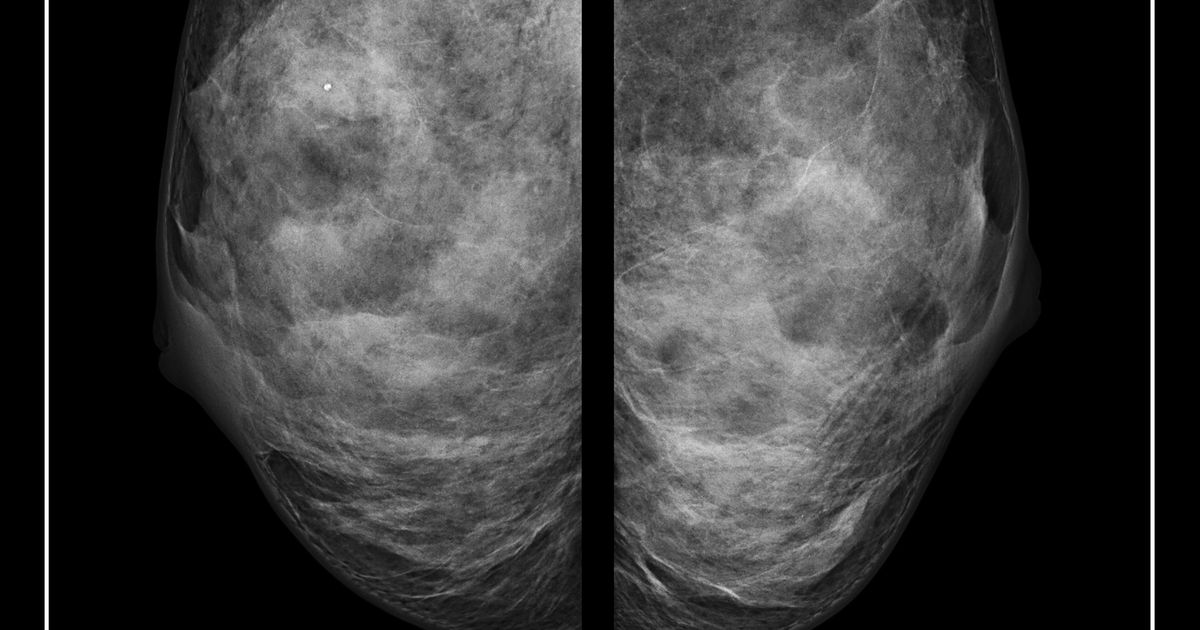

TRICARE explains which breast cancer screenings are covered and how often, including mammograms (typically annually for certain ages or risk factors), breast MRI for high-risk individuals, genetic counseling/testing, and clinical breast exams, and it clarifies the difference between screening and diagnostic tests under preventive care rules.